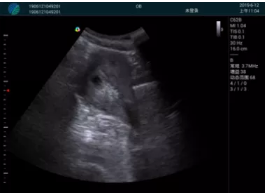

清晰顯示孕囊,通過軟件包計(jì)算孕齡7w+6d

M20實(shí)時(shí)引導(dǎo),術(shù)中清晰顯示孕囊被破壞和抽吸針的過程,清晰顯示吸引針

抽吸結(jié)束后縱切子宮,孕囊已被完全抽吸,未見明顯殘留